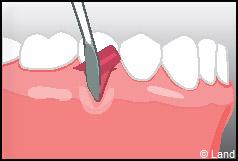

LES TECHNIQUES AVEC APPORT DE GENCIVE OU « GREFFE DE GENCIVE » :

Elles font appel à un prélèvement sur le patient à un endroit où elle est en excès, qui est ensuite posé sur la récession.

Destinées aux zones esthétiques, elles consistent à prélever la partie profonde du palais (site donneur).